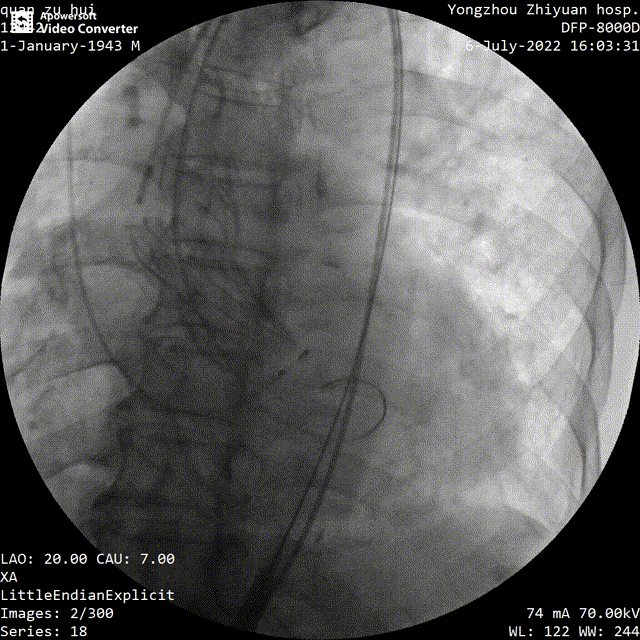

主动脉根部造影

手术过程中,在完成跨瓣操作后,23mm球囊预扩有轻微腰征、无造影剂渗漏,预装TaurusElite AV29瓣膜到位,输送系统快速、顺利地完成过弓、跨瓣操作,于瓣环上约2mm定位释放;针对本例患者瓣叶明显增厚伴重度钙化,左右窦间可见钙化融合嵴的特点,TaurusElite瓣膜高密度流入端设计提供了足够的径向支撑力,保证了瓣膜的锚定力,瓣膜内外双裙边设计能提供良好的辅助锚定力,有效减少瓣周漏。此外,本例患者左窦间存在长条状钙化延伸至瓣环下10mm水平,释放位置偏深可能存在起搏器植入风险,TaurusElite瓣膜具有多次完全可回收,回收后可重新跨瓣、释放的特点,给予术者足够的信心完成高位释放的操作,释放后最终瓣架底端位于瓣环下约1mm,实现了释放位置的精准控制,有效的减少了起搏器植入风险,确保了手术安全、顺利的完成。这例手术为永州地区开展的第一台TAVR手术,填补了该地区TAVR技术空白,标志着永州市心脏瓣膜疾病诊治迈入了全新的微创治疗时代!